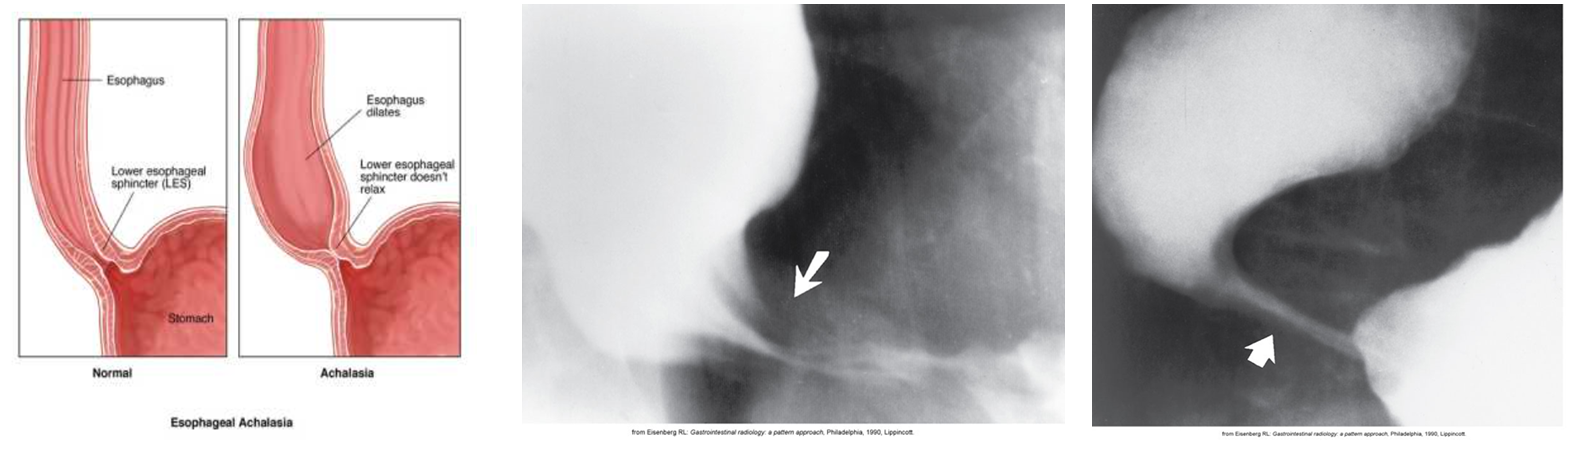

Achlasia

Functional obstruction of the distal esophagus with proximal dilation.

Caused by incomplete relaxation of the lower esophageal sphincter.

It is related to the absence of ganglion cells in the myenteric neural plexuses of the distal esophageal wall.

Radiological Appearance:

Rat Tail / Bird’s beak